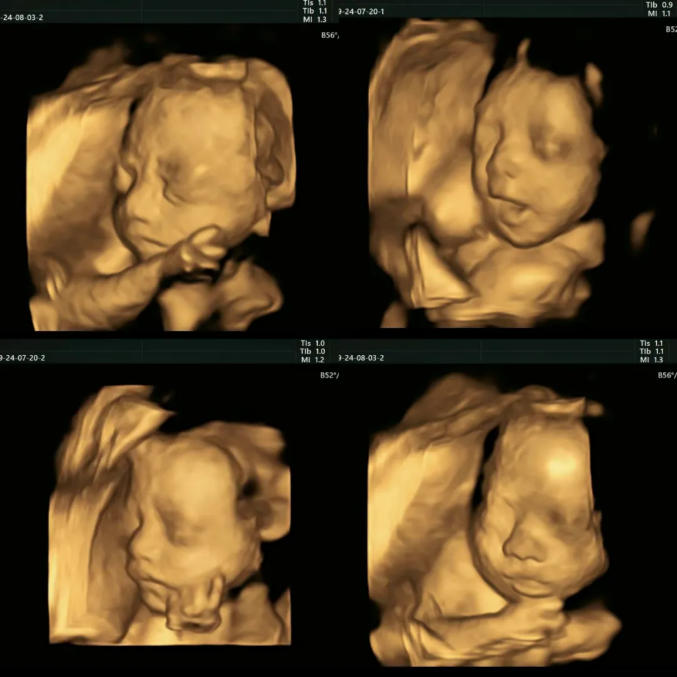

四维彩超的全称是四维彩色超声诊断仪,是现代先进的彩色超声设备。

四维彩超能够表面成像,更加清晰的筛查胎儿的四肢发育是否畸形,是否脑膜膨出,是否唇腭裂、是否脊柱裂等先天畸形,及早发现并及早做出解决方案。

准妈妈一般在怀孕20-26周时做四维彩超。

孕20周前胎儿器官、四肢未发育完全,此时检查结果准确性低。孕20周后胎儿各个器官发育良好,此时准妈妈可通过四维彩超检测胎儿是否健康。